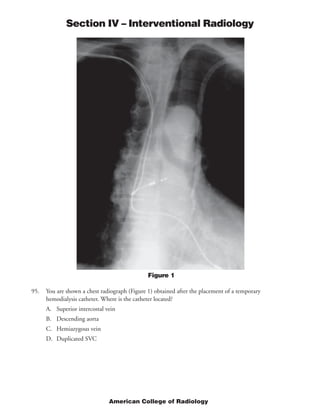

This document provides rationales for questions on the 2005 American College of Radiology Diagnostic In-Training Examination for interventional radiology residents. It includes the questions, images associated with some questions, findings for each image, and rationales for the correct answers. The questions cover topics such as locations of dialysis catheters, diagnoses for angiograms, standards for uterine artery embolization, and indications for percutaneous nephrostomy.